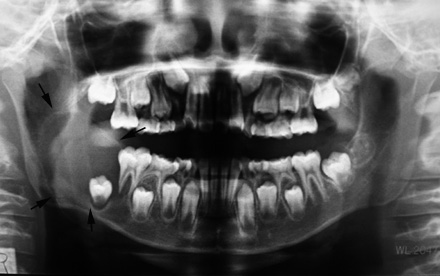

X-pでは顎骨内に単房性の嚢胞様透過像を示すエナメル上皮腫の亜型。埋没歯をともなうことがあり画像のみでは含歯性嚢胞や他の嚢胞性病変との鑑別は難しい

X-pはdentigenous cystを思わせる像だが, 上皮の性状が異なる。